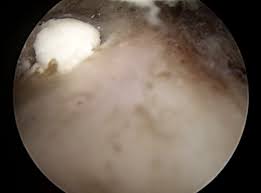

Der Verlauf der Kalkschulter variiert individuell man unterteil die Erkrankung in 4 Stadien. Eingriff dauert 20 Minuten danach ist der Kalk weg. Ob die KK Kosten übernimmt klärt sich morgen.

Die Operation einer Kalkschulter sei eine kurze unkomplizierte Sache sagt Karim Eid. Die Kalkschulter tritt bei vielen Menschen zwischen dem 30. Nicht bei jedem Patienten verläuft der Heilungsprozess gleich schnell auch wenn es. Ein schmerzarmes Initialstadium während dem es zu Umbauten im Gelenk kommt die Phase der Kalkeinlagerung in der bewegungsabhängige Schmerzen auftreten die Phase der Resorption in der die Schmerzen häufig am stärksten sind. Behandelt wird in der Regel zunächst konservativ also ohne Operation. 6 Wochen Schonung damit sich die Sehnen erholen können. Bei Behandlung durch Stoßwelle die wir regelmäßig vorziehen und mit nur wenigen Ausnahmen sehr erfolgreich finden. Man ist natürlich gehandicapt - ich sage es braucht ca. Eine halbe Stunde danach darf man den Arm sofort bewegen.

Brauche ich für eine Kalkschulter-OP eine Narkose. Die Arbeitsunfähigkeit nach Arthroskopischer Operation einer Kalkschulter kann 2-6 Wochen dauern. In der Regel tritt eine Kalkschulter zwischen dem 35. Es besteht keine Rückfallgefahr. Oftmals kommt es bei körperlichen Berufstätigkeiten zu einem Ausfall von circa drei Monaten bei schwerwiegenden Verletzungen sogar bis zu sechs Monaten und länger. Man ist natürlich gehandicapt - ich sage es braucht ca. Etwa drei Wochen jeweils einmal pro Woche 15 Minuten lang dauert.